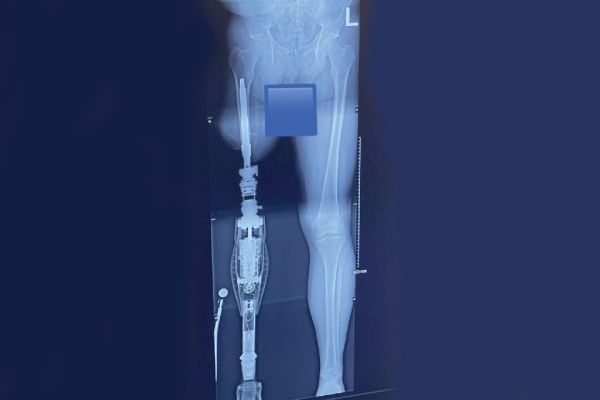

Osseointegration is now an advanced reconstructive surgery technique for amputees. The implant connects directly with the bone of the residual limb for the purpose of better body awareness and superior balance and gait. The procedure inserts a titanium implant into the marrow space of the bone. The rod becomes integrated over time to become part of the bone. The other end of the implant extends through the soft tissue for direct attachment to the prosthetic device.